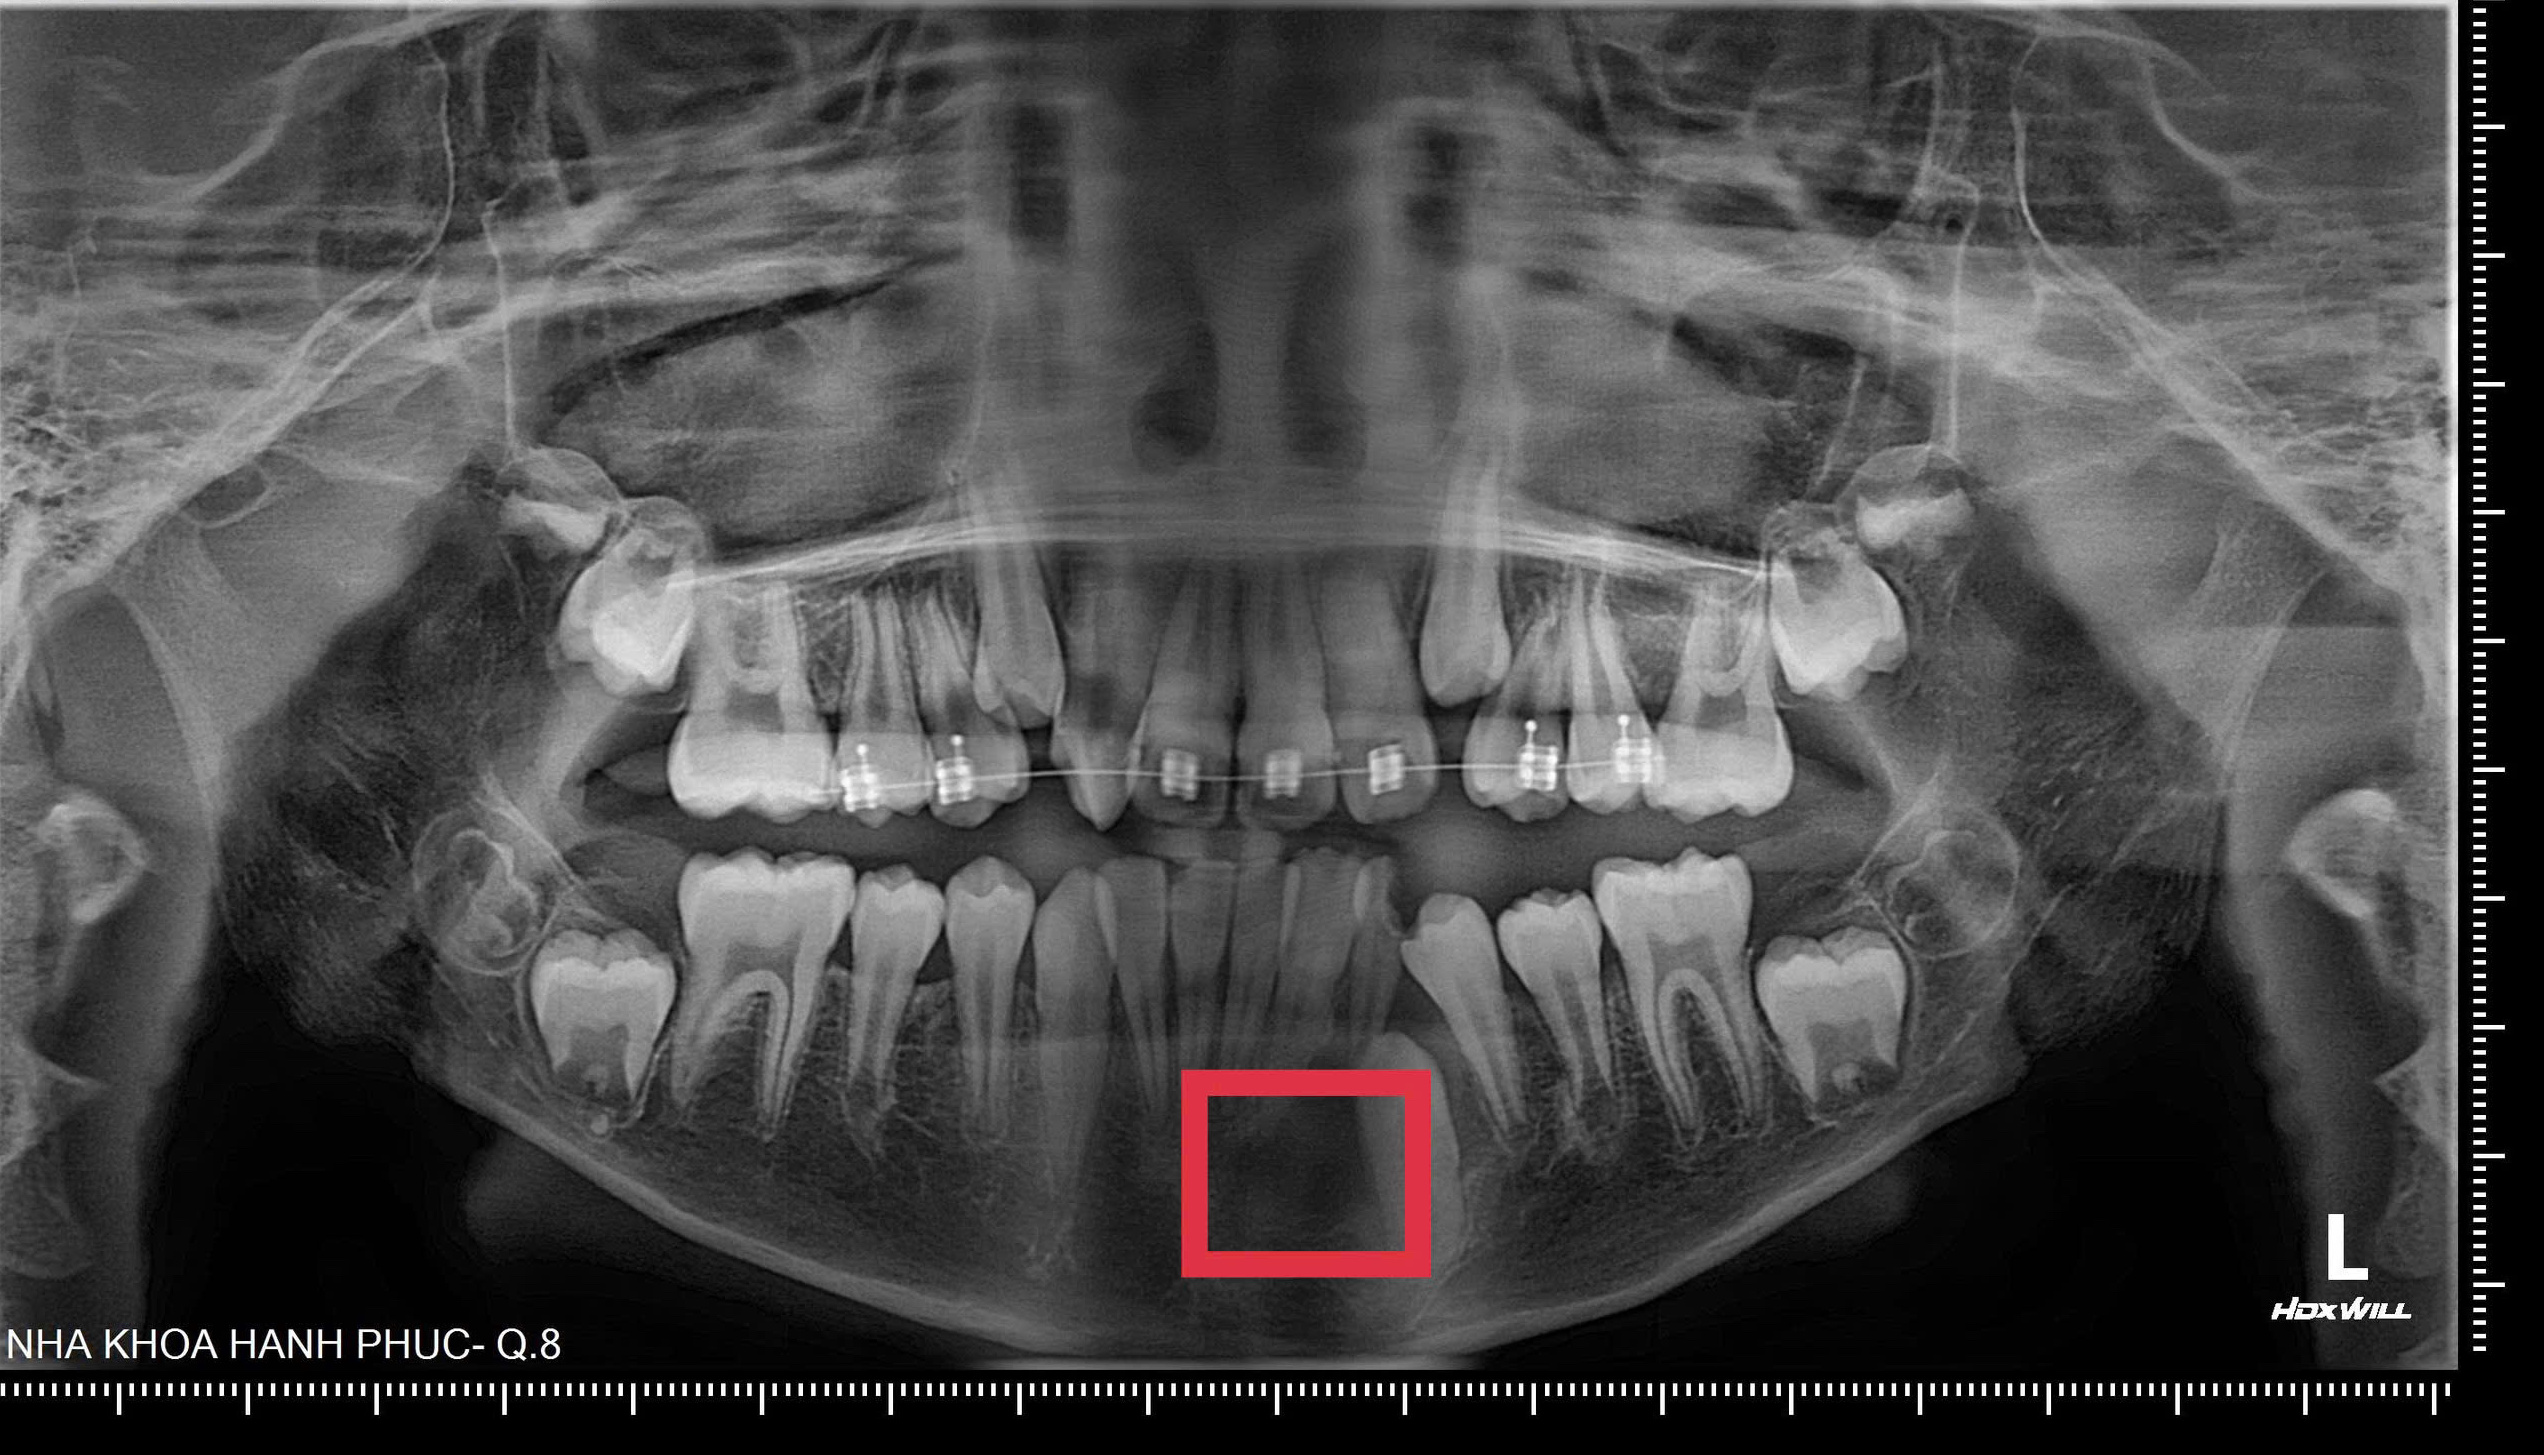

BS.CK1 Phan Bá Ngọc - Giám đốc Phòng khám Nha khoa Hạnh Phúc cho biết, kết quả kiểm tra trong miệng cho thấy, bé đã thay gần hết răng, chỉ còn một răng sữa là răng R73. Răng này sâu lớn phần thân và có dấu hiệu viêm. Khi chụp phim Panorama và Conebeam CT, bác sĩ phát hiện răng R73 đã sâu đến tủy, tủy hoại tử, tạo thành một nang lớn phía dưới, làm phá hủy xương hàm và lan sang hai răng bên cạnh. Nếu không phát hiện kịp thời, nang có thể tiếp tục ăn rộng, ảnh hưởng đến mầm răng vĩnh viễn và cấu trúc xương hàm của trẻ.

Bác sĩ đã chỉ định nhổ răng sữa viêm, đặt dẫn lưu nang và theo dõi cho đến khi răng R33 mọc lên ổn định, sau đó mới bắt đầu quá trình niềng răng theo đúng kế hoạch.